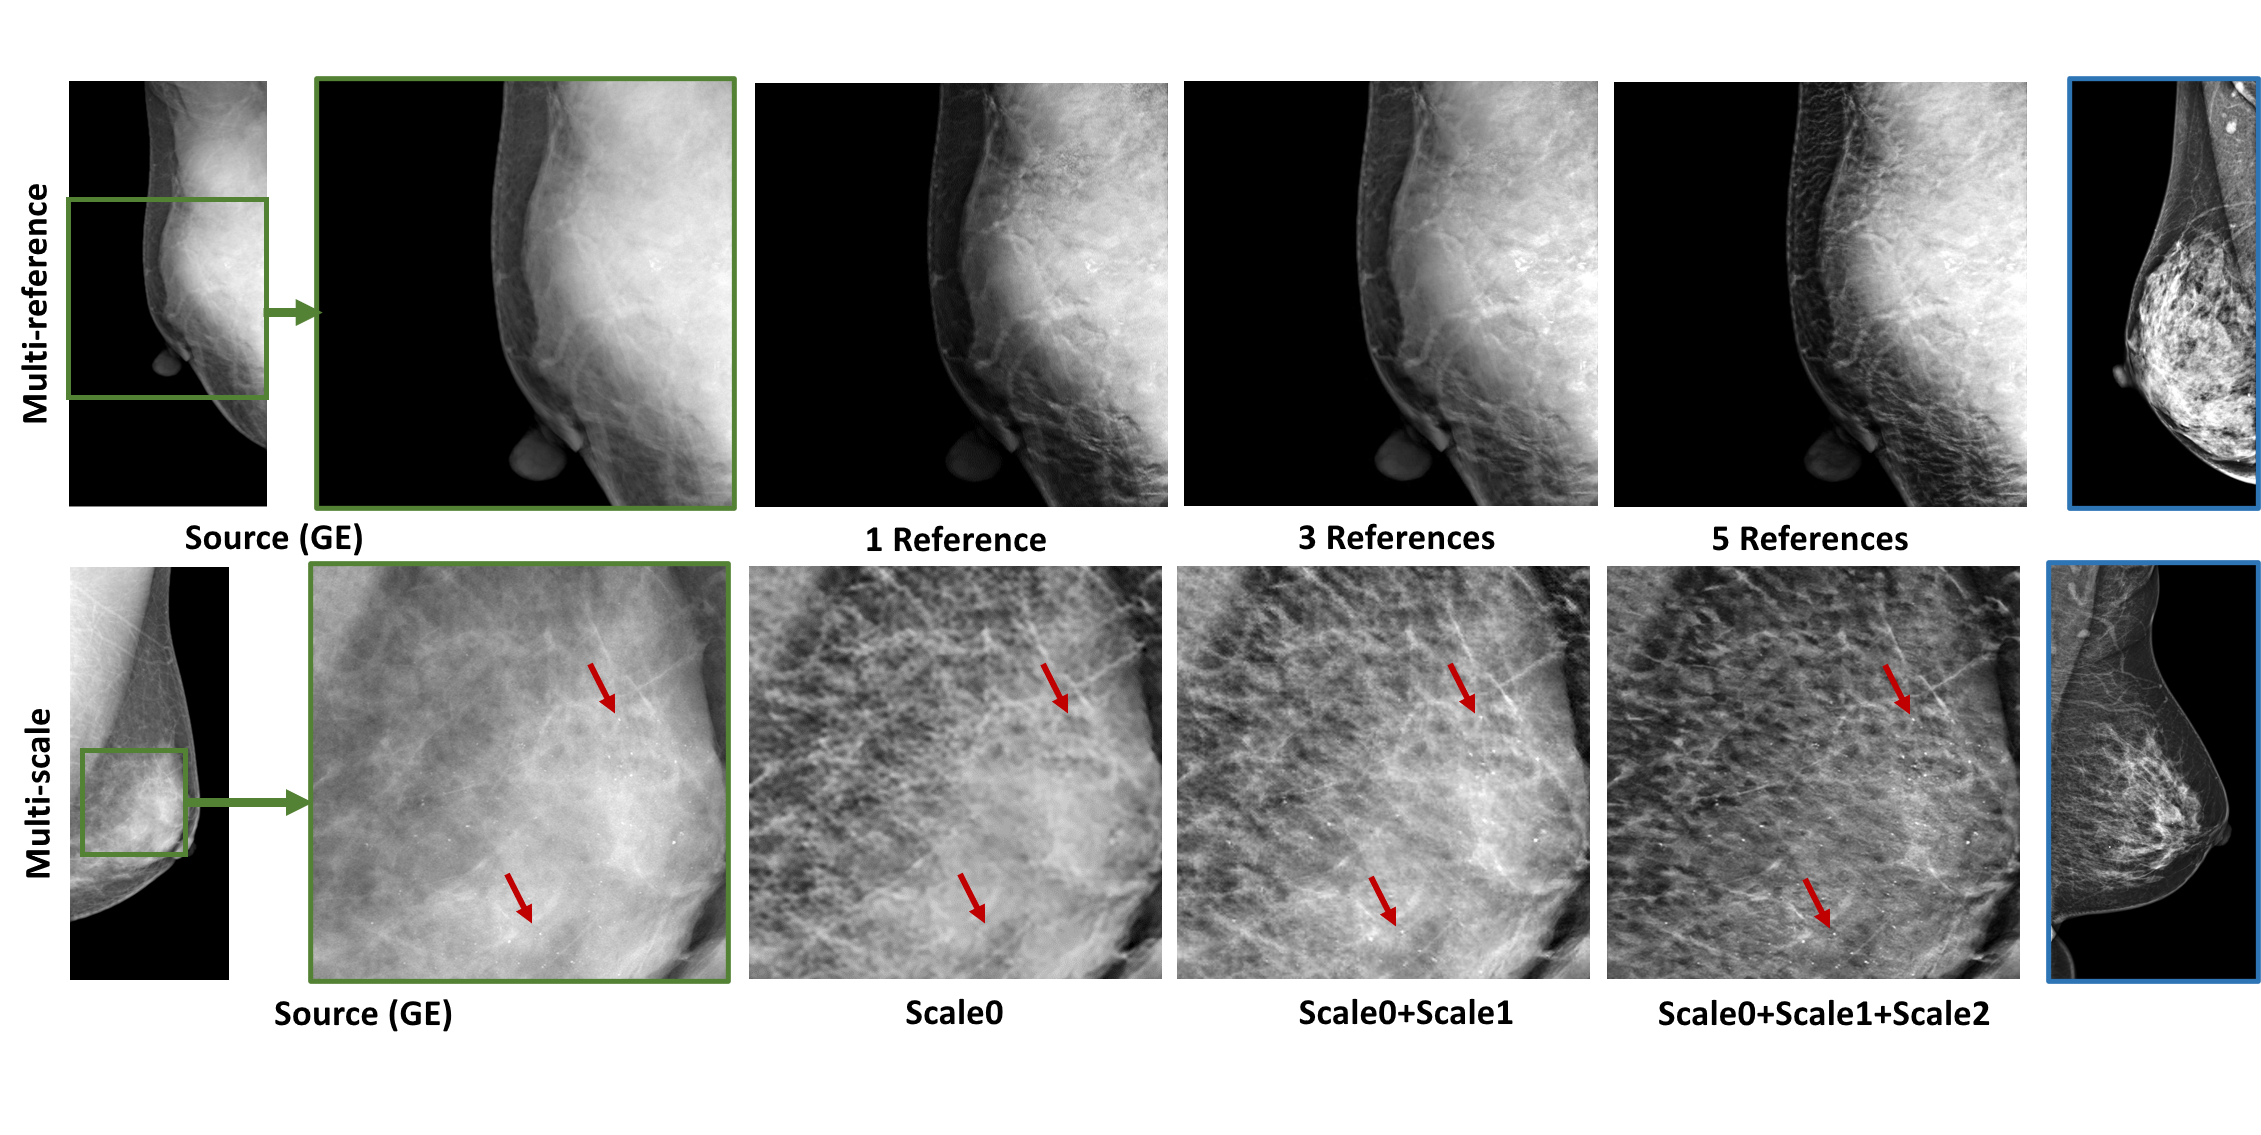

Refer to caption

Figure 3: The visual illustration of the multiple reference and multiple resolution effect. The red arrows suggest the calcifications or μ𝜇\muCs in the images.

Fig. 3 illustrates the efficacy of multi-reference and multi-resolution scheme for the mST from GE to UIH. The upper row in Fig. 3 shows better enhance on glandular tissues with 5 reference images on a case with high density, while the lower row suggests the calcification can be better enhanced by fusing the transferred images from all three scales. Fig. 4 shows the mST results from our mr2NST and the baselines of cycleGAN and EHM. From visual comparison, the quality of the transferred images from mr2NST are much better. The cycleGAN requires large GPU memory and can’t support mST in high resolution. Meanwhile, referring to the right part of Fig. 4, mr2NST can preserve the details of vasculature after the mST.